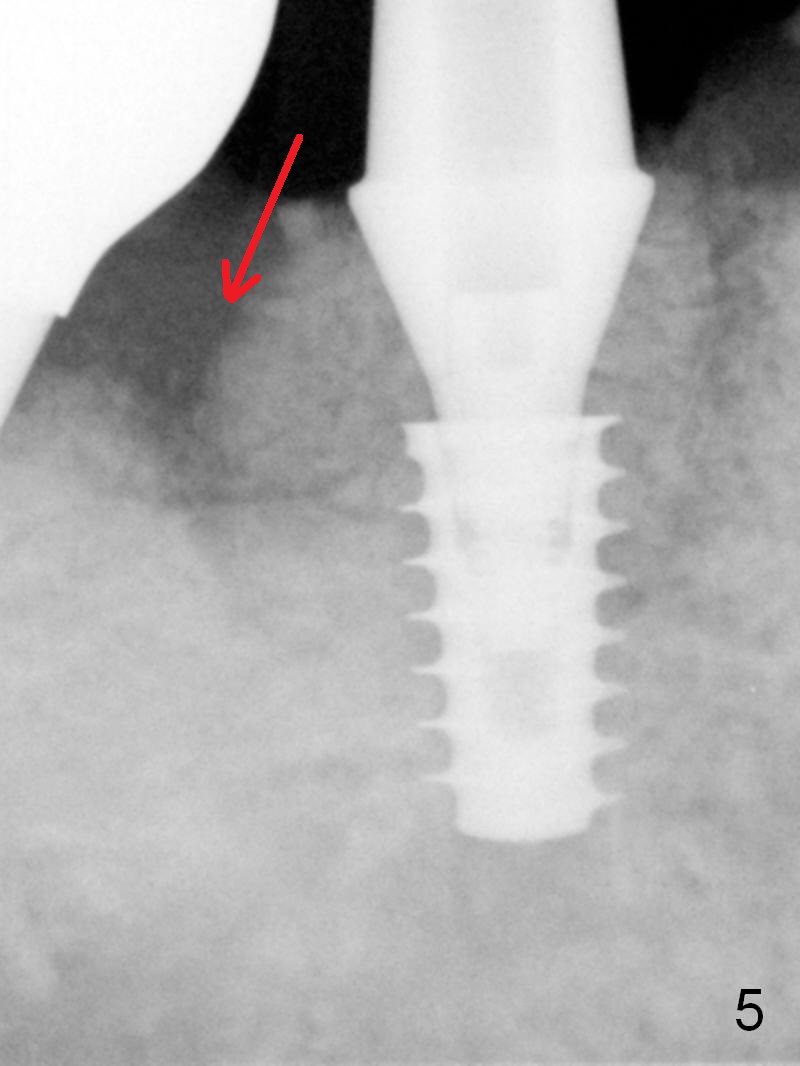

A 5x9 mm implant is placed with packing abundant allograft (.5-1.5 mm) and Osteogen; it appears that 3 to 4 threads (fins) of the implant are engaged to the native bone for primary stability (>40 Ncm). Later more bone graft is placed distally (Fig.5 arrow). Abutment: 6.5x5.5(4) mm.